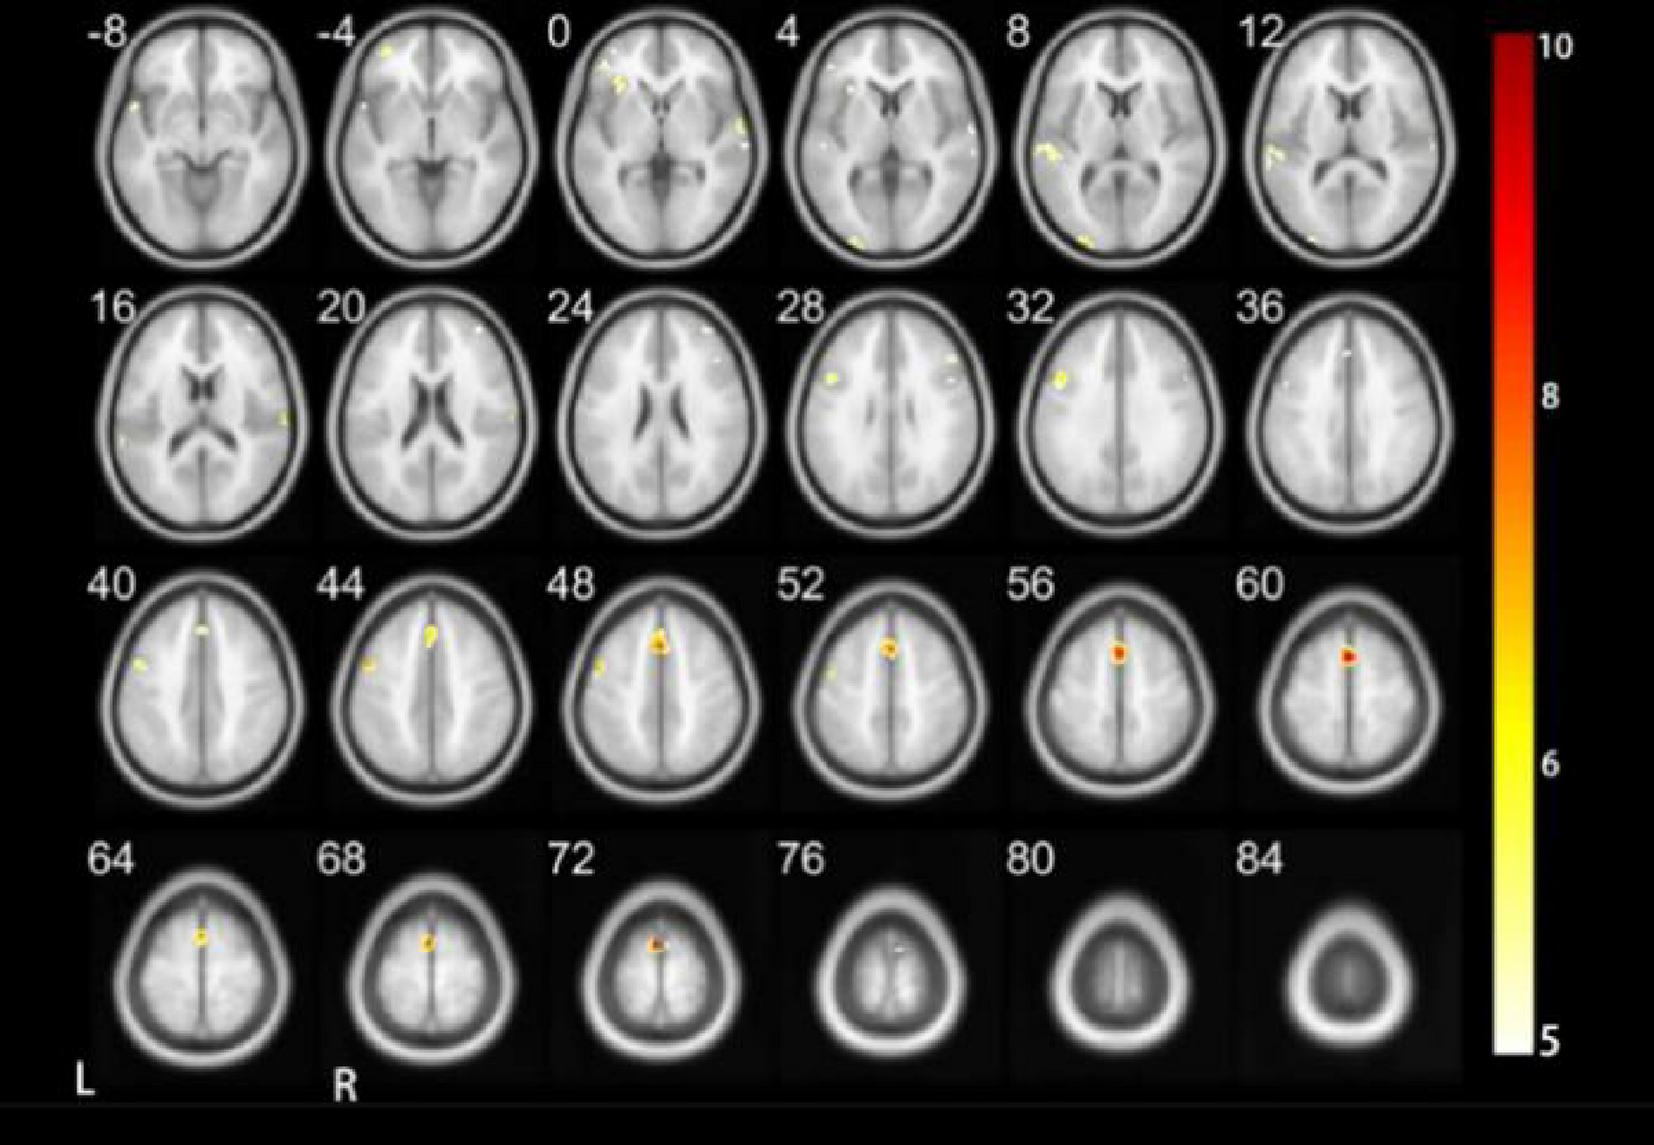

Results of DC when performing the tone three task.